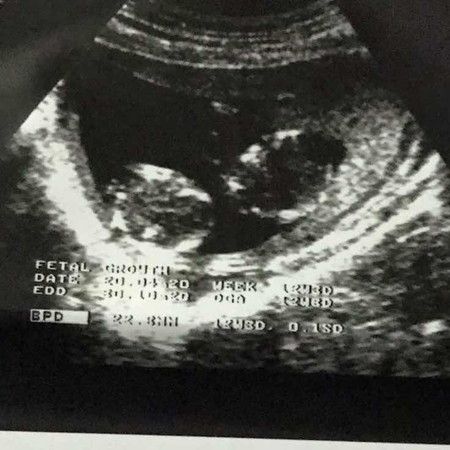

scan 13 weeks kembar

salam, normal ke 13 weeks macam ni ? saya first time pregnant & doctor cakap kembar ?

Walaaikumsalam, tahniah sis nampak mcm ada dua kantung ❤️